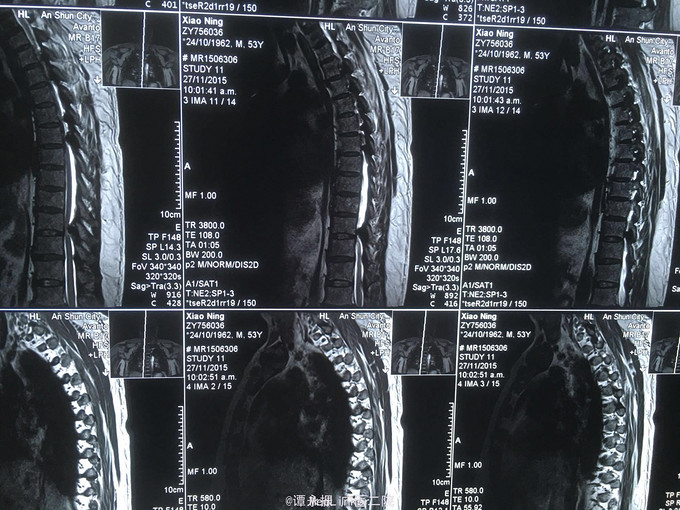

黄韧带怎么啦?

一位从贵州过来的善良妇女转述他哥哥的主诉“下肢麻木伴行走困难半年”,以下是当地县医院的MRI!向各位专家求原因和治疗方法!

颈椎黄韧带骨化